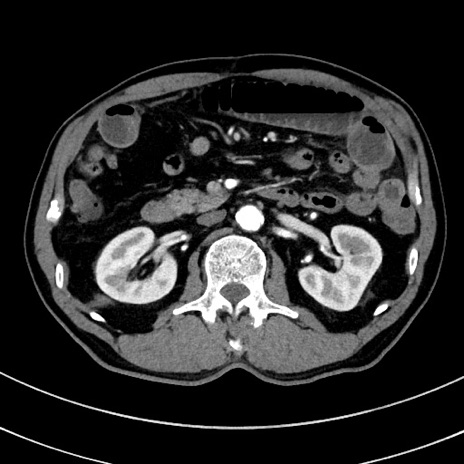

症例8(横断像)

【症例】 60歳代男性

【主訴】 黒色吐物

【現病歴】 4日前から嘔気自覚、2日前の朝食後にも嘔気あり、自分で手で嘔吐反射起こし嘔吐したところ血が混ざっていたため受診。

【既往歴】 5年前汎発性腹膜炎を伴う急性虫垂炎で手術、高血圧、前立腺肥大症、高脂血症

【身体所見】 腹部正中に手術癩痕あり 腹部平坦・軟圧痛なし膨満感あり

【データ】WBC 8400、CRP 4.54